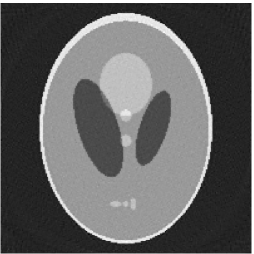

Noised projection data: For the noised projection data, the iteration processes were terminated when for 82 and 112 projections. The reconstruction images were given in Fig. 7. Table 4 showed the MSEs, iterations and running time of program of the results of images in Fig. 7.

| Algorithm | TVS | TV-PPS | TVS | TV-PPS |

|---|---|---|---|---|

| projections | 112 | 112 | 82 | 82 |

| iterations | 3 | 7 | 13 | 13 |

| MSEs | 0.0102 | 0.0080 | 0.0164 | 0.0158 |

| RT(min) | 2.0529 | 5.1975 | 10.382 | 9.1644 |

By comparing the images in Fig. 6, 7 and numbers in Table 3, 4, we can obtain the same conclusions that the proposed perturbation can not only improve qualities of reconstructed images, but also can accelerate the convergent speed. However, we can observe that the reconstruction images suffer from artifacts regardless of the classic and the proposed algorithm when the projections is inadequate.